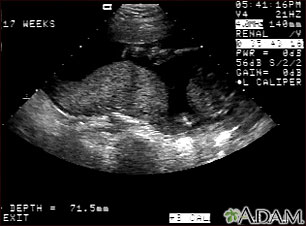

This is a normal ultrasound performed at 17 weeks gestation. It shows the placenta during a normal (Braxton Hicks) contraction. Throughout the pregnancy, the uterus periodically contracts to facilitate better blood flow through the placenta and the fetus. In this ultrasound, the placenta can be seen as the mound-shaped object in the middle of the screen. At the bottom of the image, the mother's vertebra can be seen as a round object. When the uterus is not contracting, the placenta would appear much flatter.